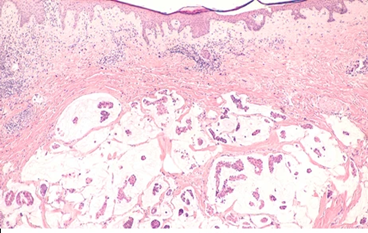

1. Ductal Carcinoma In Situ (DCIS)

Ductal Carcinoma In Situ (DCIS) is a non-invasive type of breast cancer. Cancer cells in DCIS are contained in the milk ducts and have not invaded nearby tissue. It has also been called Stage 0 breast cancer. While it’s not invasive, if not treated, over time it could progress to invasive cancer.

2. Invasive Ductal Carcinoma (IDC)

Invasive Ductal Carcinoma (IDC) is the most prevalent form of breast cancer and represents about 80% of all cases. IDC originates in the milk ducts and subsequently spreads to the surrounding tissues. IDC has the potential to spread to the lymph nodes and to the rest of the body if not diagnosed early.

- Cribriform Carcinoma: Presents as a sieve-like structure under the microscope.